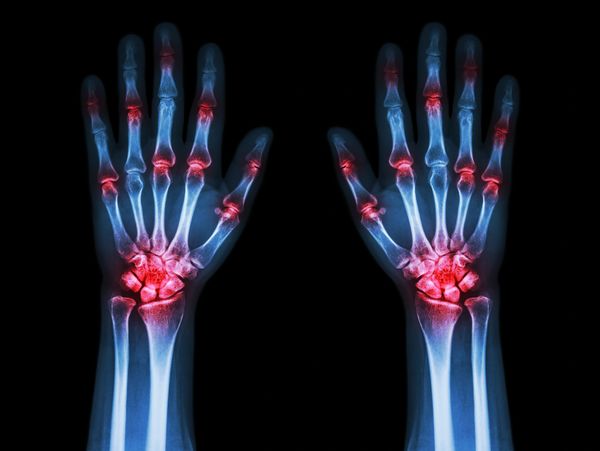

Joint pain can be felt in multiple parts of the body including knee joint pain, sacroiliac joint pain, hip pain and shoulder pain. Age, weight, previous injuries or surgery, overuse and other conditions can be factors causing joint pain.